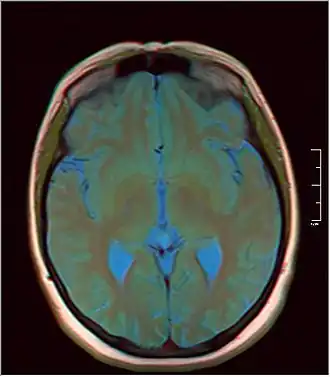

MRI axial in false color -